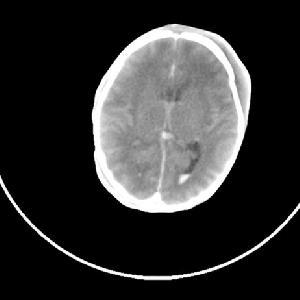

新生儿颅内出血的严重程度与出血部位和出血量有关,出血轻的患儿可以没有任何症状,但严重的可以在短时间内死亡。

颅内出血的临床表现为精神和神经的一系列症状:

1、烦躁不安,容易发火,嗜睡,甚至昏迷。2、呼吸节律不齐,甚至暂停。

3、前囟隆起,血压增高,抽搐,角弓反张,尖叫。

4、凝视,斜视,眼球震颤,瞳孔不等大,对光反射消失。

5、原始的反射减弱或消失,如膝跳反射,排便反射。

6、低体温,贫血,黄疸等症状出现时,应该考虑颅内出血的可能性。